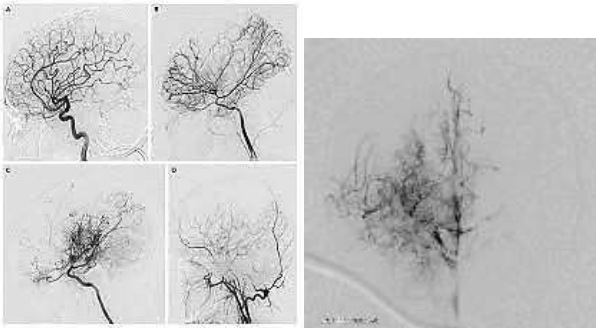

Paciente de 7 anos, sexo feminino, é atendida em unidade de urgência com episódios recorrentes de cefaleia e déficit motor dimidiado temporário. Em investigação complementar realiza estudo angiográfico que demonstra os achados de imagem abaixo.

Baseado no caso e nas imagens apresentadas, assinale a alternativa correta.